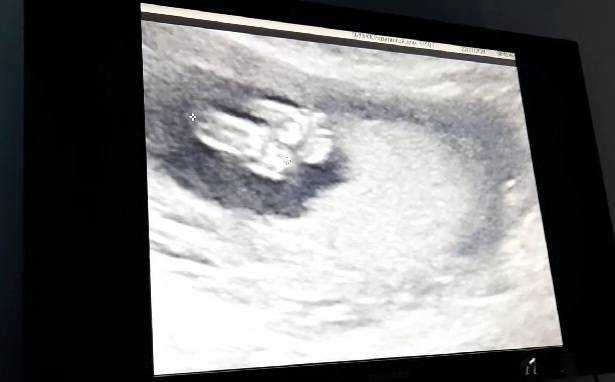

На фото наши пяточки)))

#16недель